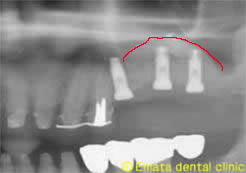

レントゲンでもサイナスは挙上でき3本インプラントが埋入できました。

After